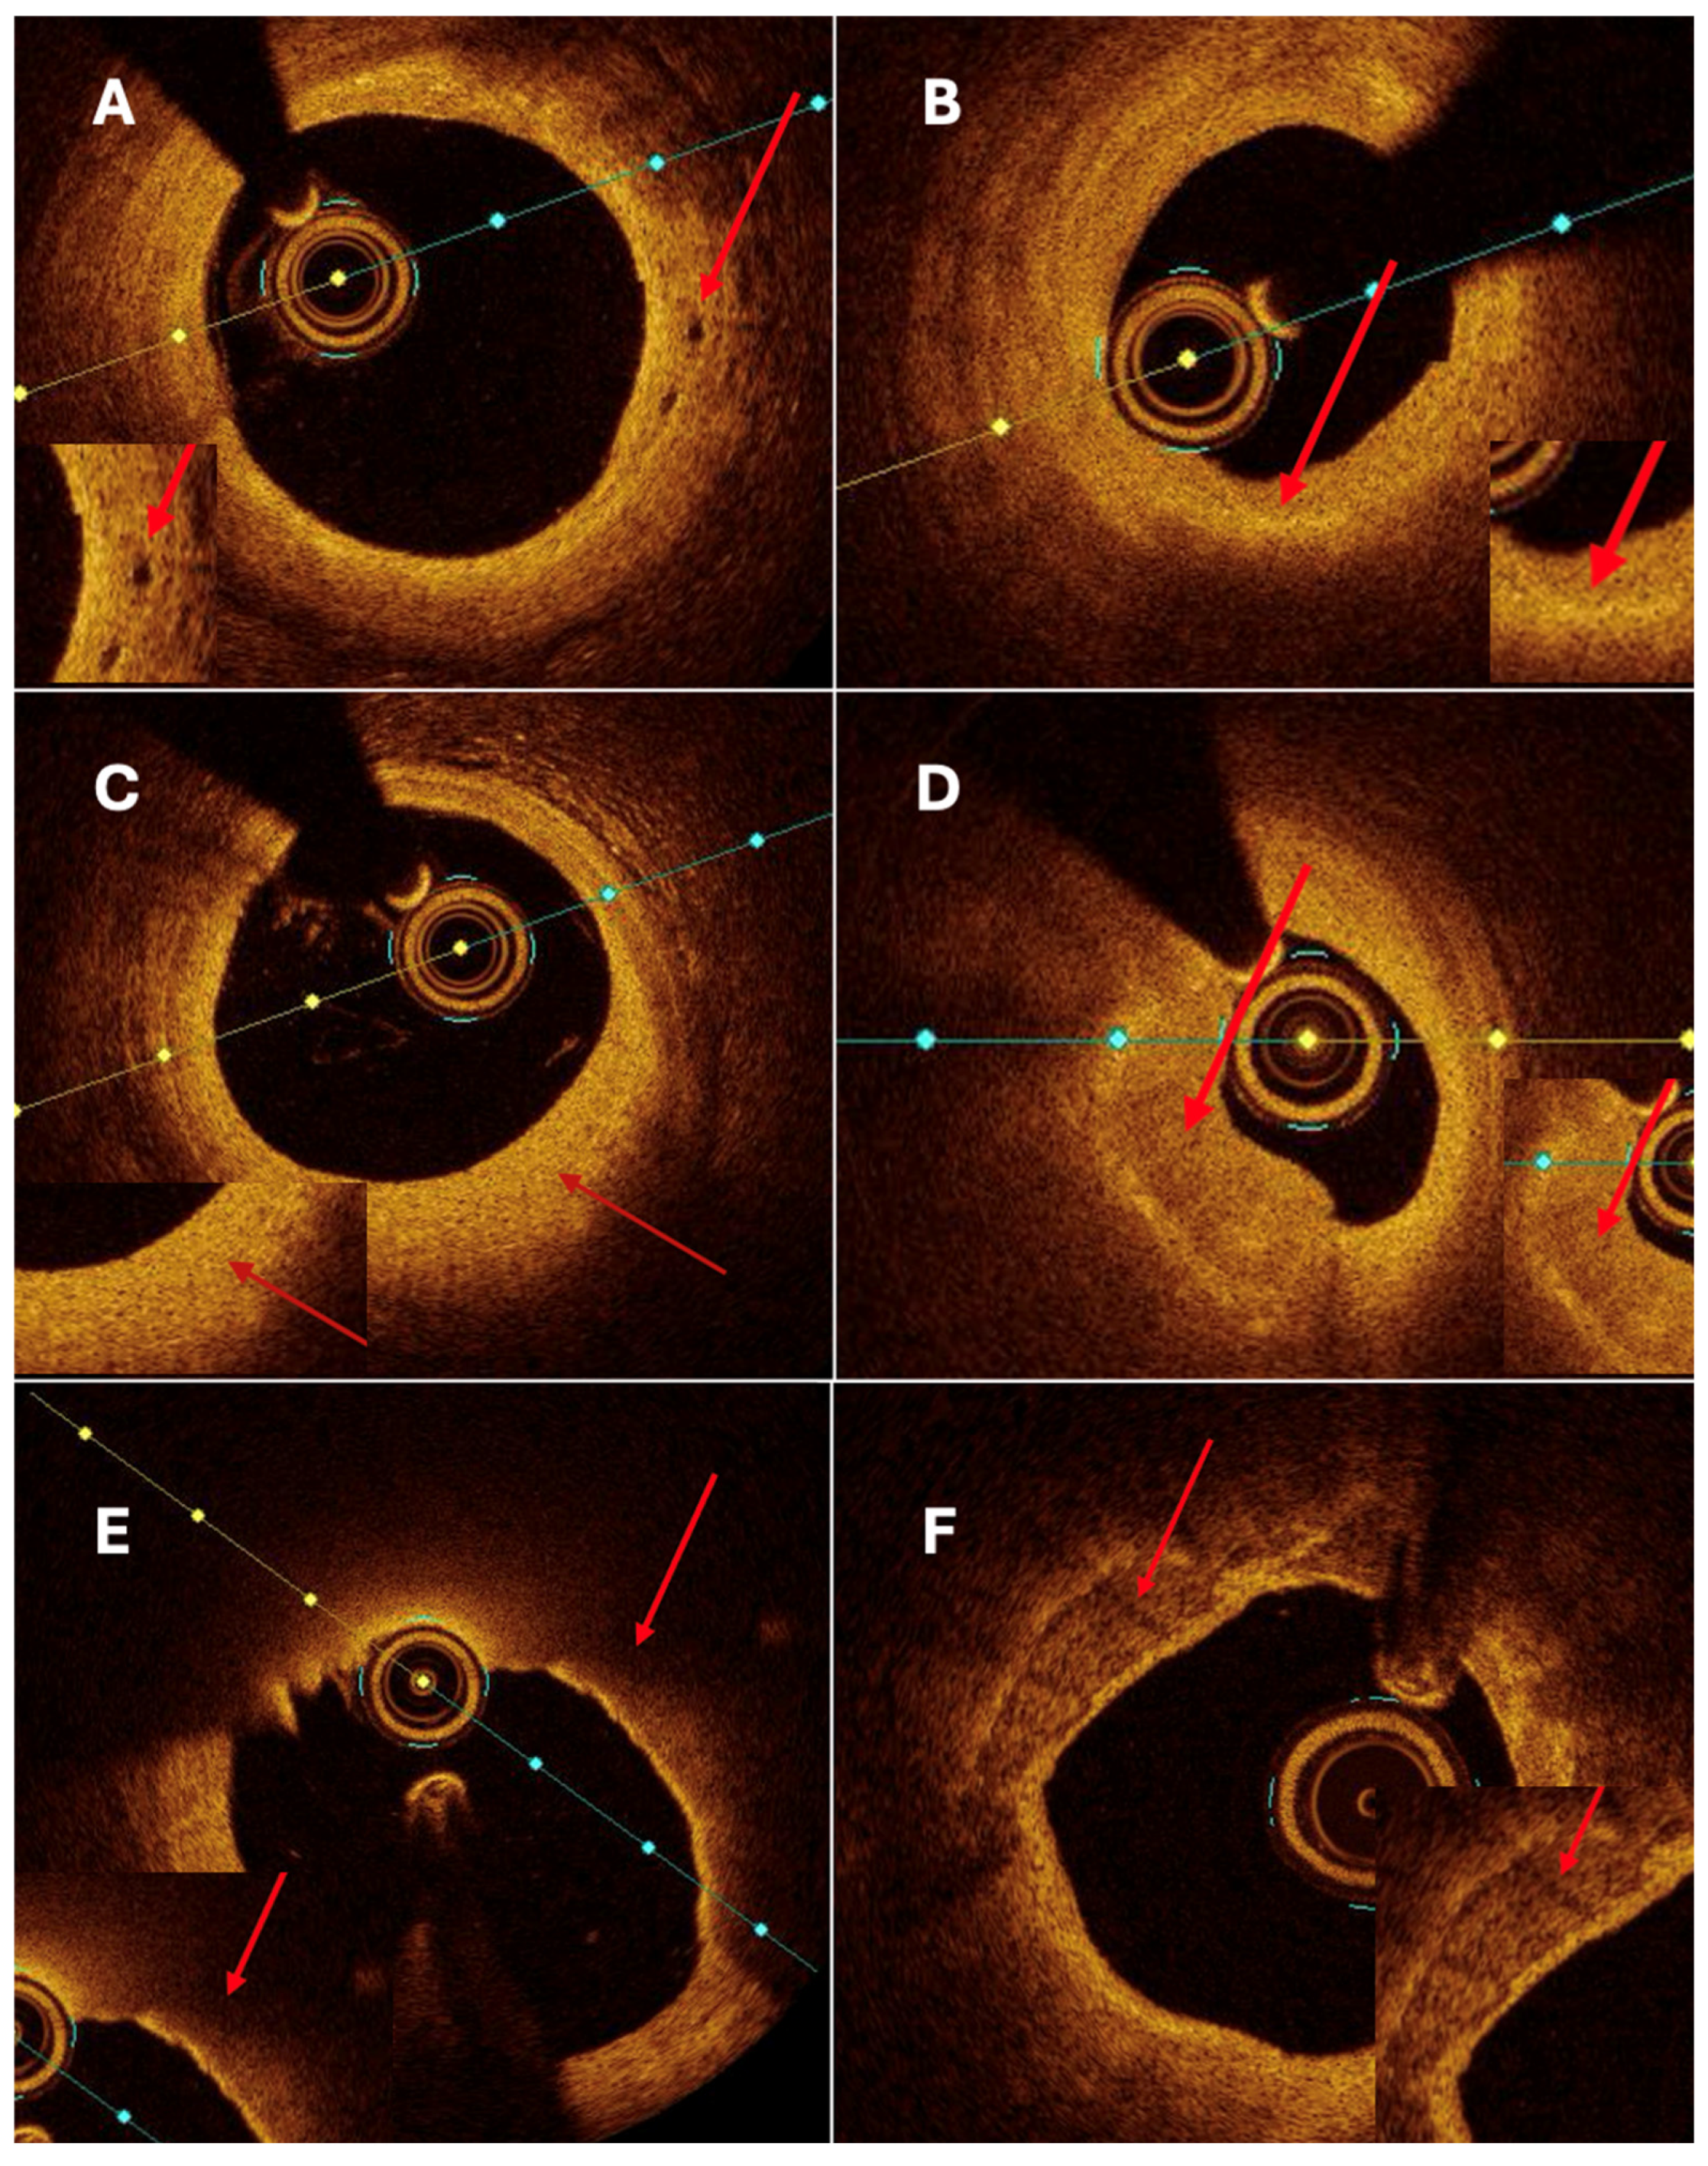

5]. Based on the extent of arterial involvement and the relationship between the transverse and longitudinal dimensions, two morphological types are distinguished: coronary artery ectasia (CAE), defined as a diffuse dilatation involving at least one-third of the vessel length, and coronary artery aneurysm (CAA), a focal dilatation that may be saccular or fusiform (

Figure 1). In both CAE and CAA, the dilated segment exceeds the reference vessel diameter by ≥1.5-fold.

CAAE encompasses two phenotypes: CAE, defined as a diffuse dilatation of a coronary artery to ≥1.5 times the diameter of an adjacent normal reference segment that involves at least one-third of the vessel length, and CAA, defined as a focal dilatation of a coronary artery to ≥1.5 times the diameter of the nearest normal segment (

Figure 1). CAA is morphologically classified as saccular when the transverse diameter exceeds the longitudinal dimension and as fusiform when the longitudinal dimension exceeds the transverse diameter with circumferential, spindle-shaped involvement of the vessel. A “giant” CAA is commonly designated when the diameter exceeds four times the reference caliber or is greater than 8 mm.